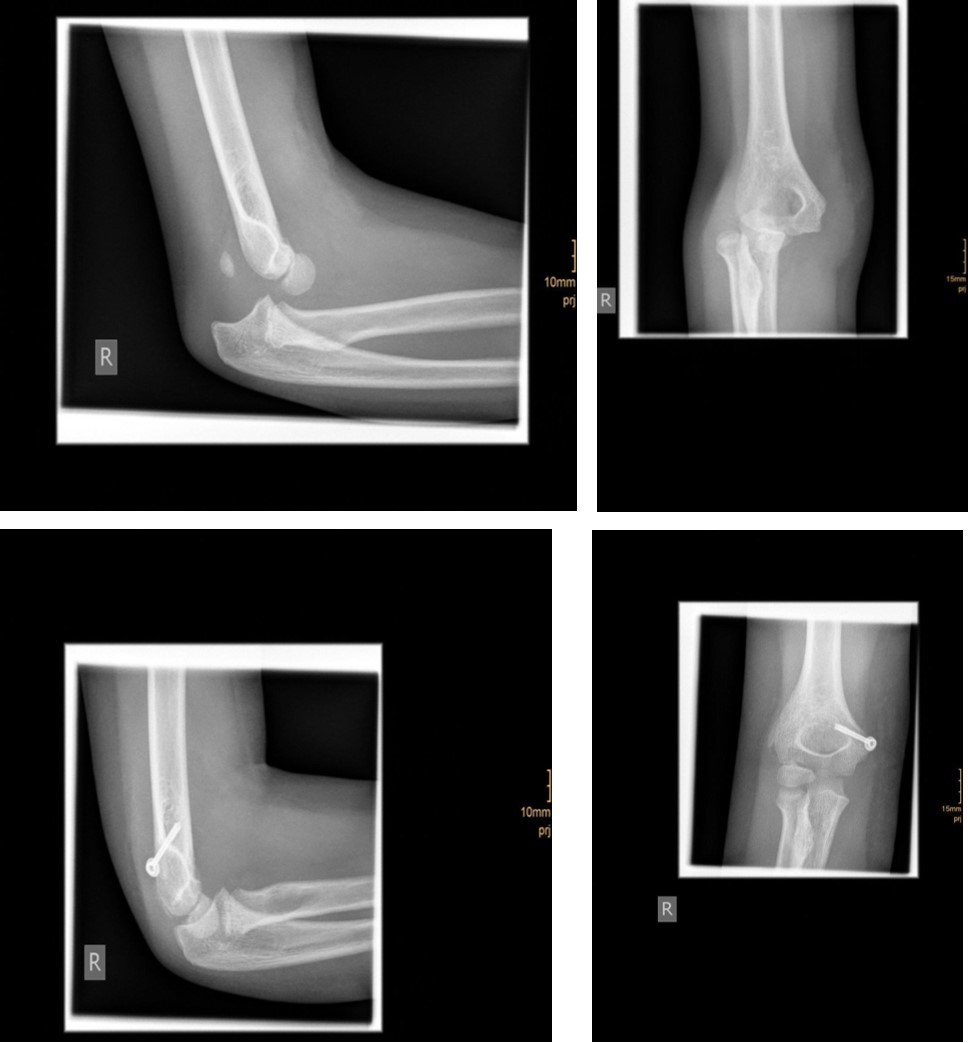

The fracture fragment can be approached by a posteromedial incision that allows good exposure of both the fracture site and the ulnar nerve. Fixation is easily achieved with smooth K-wires or with screws in older adolescents. Two wires are necessary because of the sagittal rotation forces exerted on the fracture fragment by the common flexor muscles. Figure 4 and Figure 5.

Figure 5.9 year old female patient with a elbow dislocation and a dislocated right medial condyle fracture which was treated by open reduction and osteosynthesis with a screw (personal collection)